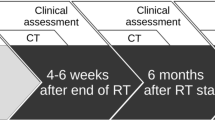

All patients were monitored for RP on an outpatient basis with chest X-ray examinations. Additionally, a CT scan was requested if they were suspected to have RP. Otherwise, a CT scan was basically planned at 1 month after radiotherapy and every 3–6 months thereafter [20]. RP was graded according to the Common Terminology Criteria for Adverse Events, version 3.0 (CTCAE ver. 3.0). For this study, the onset of RP was recorded by radiologists based on CT findings taken either as planned or upon request.

Grade 2–5 RP was recognized in eight (13 %) of the 62 patients: Grade 5 in three patients and Grade 2 in five patients. RP occurred between 1.8 and 6.4 months (median 4.7 month) after the start of thoracic RT. Table 2 shows the relationships between the clinical factors and Grade 2–5 RP in all patients. Subclinical ILD was a significant factor predicting the occurrence of Grade 2–5 RP (p = 0.0274). Grade 2–5 RP was observed in four (36 %) of the 11 patients with subclinical ILD. Subclinical ILD tended to be a significant factor associated with the occurrence of Grade 5 RP (p = 0.0785); two patients with subclinical ILD, one patient without ILD and two of the three patients with Grade 5 RP had an ILD score of 3 (Table 3; Fig. 2). All of the patients with Grade 5 RP exhibited extensive RP beyond the irradiated field, including the contralateral lung. Analyses of the correlation between the ILD score on CT and the RP grade using Spearman’s correlation coefficient showed these parameters to be significantly related (Table 4; r = 0.253, p = 0.048).

A case with Grade 5 RP (case 1 in Table 4). a, b CT images prior to thoracic RT. A score of 3 for subclinical ILD was recognized. c CT with dose distribution. Red, light blue, yellow, green and blue lines are 50.4, 45.4, 25.2, 15.1 and 2.0 Gy, respectively. d A CT image taken 1.8 months after the completion of thoracic RT showed extensive ground-glass abnormalities and focal consolidations